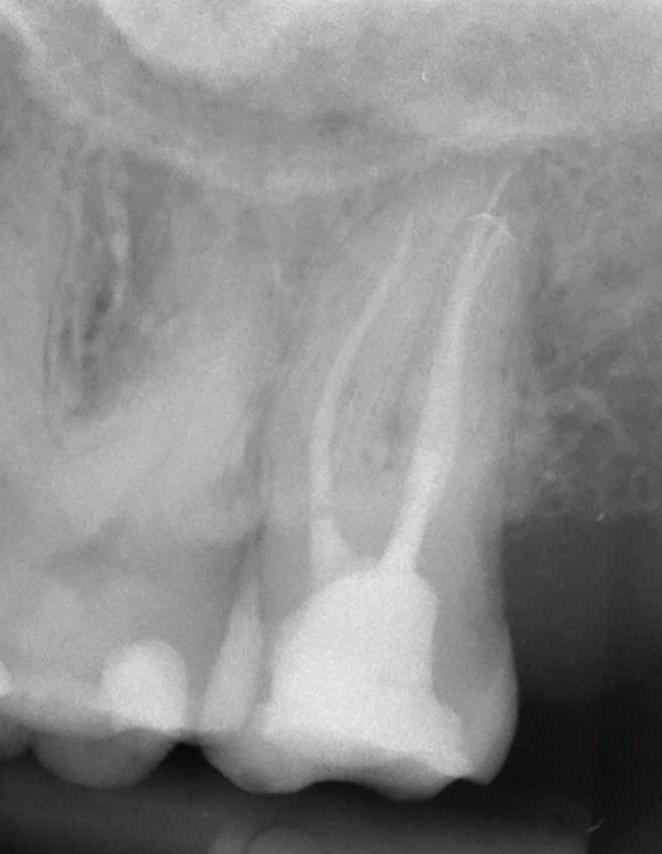

Abb. 2: Messaufnahme zur Längenkontrolle.

Nach der Oberflächenanästhesie und Betäubung des betroffenen Zahnes wurde zur Durchführung der Aufbereitung standardmäßig ein Kofferdam gelegt. Durch das zusätzliche Abdichten des Kofferdams mit flüssigem Kofferdam wurde dabei effektiv verhindert, dass Spülflüssigkeiten in den Rachen der Patientin liefen. Dies war auch deswegen von Vorteil, da die Behandlung durch eine geringe Mundöffnung zusätzlich erschwert war. Nach Eröffnung des Zahnes wurden die einzelnen Wurzelkanäle sondiert und unter dem Operationsmikroskop mit einer diamantierten Ultraschallspitze erweitert. Die Bestimmung der jeweiligen Arbeitslängen erfolgte mithilfe eines Apex Locators. Eine zur Kontrolle durchgeführte Messaufnahme zeigte, dass die Längen mit den elektronischen Messungen übereinstimmten (Abb. 2).